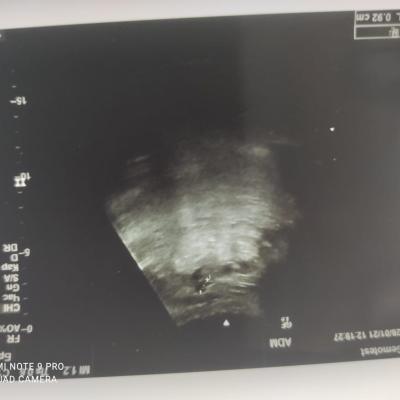

Здравствуйте! При наличии коралловидного камня правой почки(заключение УЗИ), можно предположить причиной боли нарушение уродинамики верхних мочевых путей), что, однако, не подтверждается результатами УЗИ почек( ЧЛС не расширена). Другая, наиболее вероятная возможная причина "боли в боку" - может быть патология опорнодвигательного аппарата. Необходимо проконсультироваться с неврологом и урологом очно, и согласовать возможность применения противовоспалительных, обезболивающих и спазмолитических препаратов - как первый шаг. В дальнейшем необходимо планировать возможное дальнейшее обследование и лечение. Удачи!